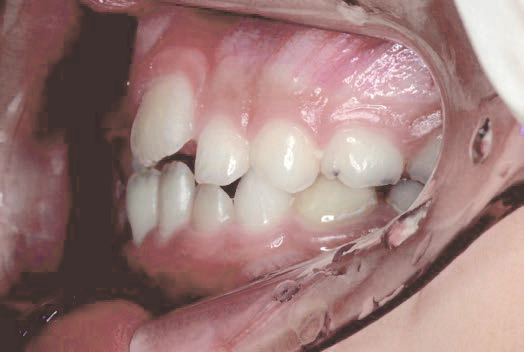

出っ歯

あごや骨格を正しく成長させる矯正治療

Aさん (矯正開始時:8歳)

Before

After

鼻がつまりやすく、口呼吸をしているために上あごが狭い状態でした。また上の前歯がかなり前へ傾いているため、お口をきちんと閉じていることができません。さらに、下の前歯もでこぼこしていました。

治療を終えて

装置によって上あごを拡大し、下あごを少し前へ成長させたことで、永久歯がきれいに並ぶスペースを確保しました。また、お口の機能が向上したことから鼻がよく通るようになり、口呼吸も改善され口も閉じやすくなったので顔の表情もよくなりました。

主訴・治療内容 下あごが後ろに下がり、出っ歯のようになっていることを心配して、無料相談に来院されました。

治療期間 2年半

費用 462,000円(税込)